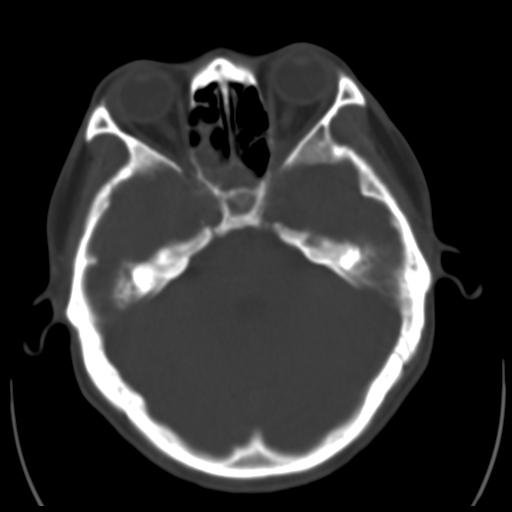

35m 鼻子时不时流血,头及右侧面部痛,颈部淋巴结未见明显大

骨窗

这个东西大家仔细看看呀

蝶窦,后组筛窦及鼻咽部团块状软组织影,骨壁破坏,病变较广泛。考虑恶性肉芽肿。建议活检。

颅底骨质明显破坏 支持鼻咽癌 但病灶的边缘毛糙 不能除外炎性

考虑中线肉芽肿(鼻硬结病),次之tb或真菌感染性肉芽肿,病变形态不像肿瘤,建议增强及活检。

蝶窦,后组筛窦及鼻咽部团块状软组织影,骨壁破坏,病变较广泛。考虑炎性肉芽肿性病变可能。建议活检。